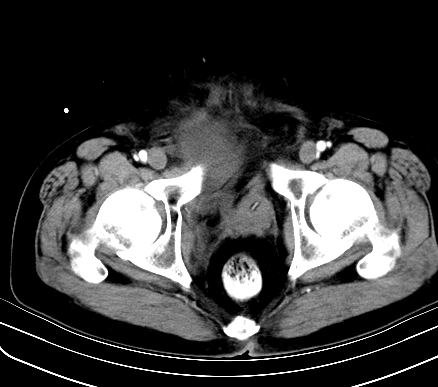

标题: CT19729B:男,74岁,因腿疼就诊,查体触腹部肿物,

增强扫描

动脉期

【临床症状】

分析:

1、老年男性,易患恶性肿瘤;

2、腿痛就诊,一部分恶性肿瘤的患者会分泌一种激素,使凝血机能发生障碍,促下肢静脉血栓形成,致腿痛,有时往往为首发症状。因此,肿瘤不除外恶性肿瘤。

【ct表现】

1、肿块巨大,往往位于腹膜后,长大后才引起症状而就诊;那么位于腹膜后的肿瘤80%为恶性肿瘤。

2、实性肿瘤,增强扫描轻度不均强化,实性肿瘤一般不是好东西。

3、肿瘤边缘似见少许脂肪样密度。

4、腹膜后未见肿大淋巴结,但肿瘤于临近的肠管及组织接触紧密。

【诊断】

腹部占位,考虑位于腹膜后的恶性肿瘤,脂肪肉瘤(实体型)可能性大。

【分析】

1、腹膜后的肿瘤少见,但种类繁多,包括脂肪肉瘤、纤维组织细胞肉瘤、纤维肉瘤、平滑肌肉瘤、恶性畸胎瘤、神经肉瘤、神经母细胞瘤、血管肉瘤及横纹肌肉瘤等,其中脂肪肉瘤为较常见的一种肿瘤。

2、增强扫描强化不明显,除脂肪肉瘤以外,一般肿瘤强化中度以上。脂肪肉瘤可不强化或轻度强化。

术后病理结果:腹膜后脂肪肉瘤。